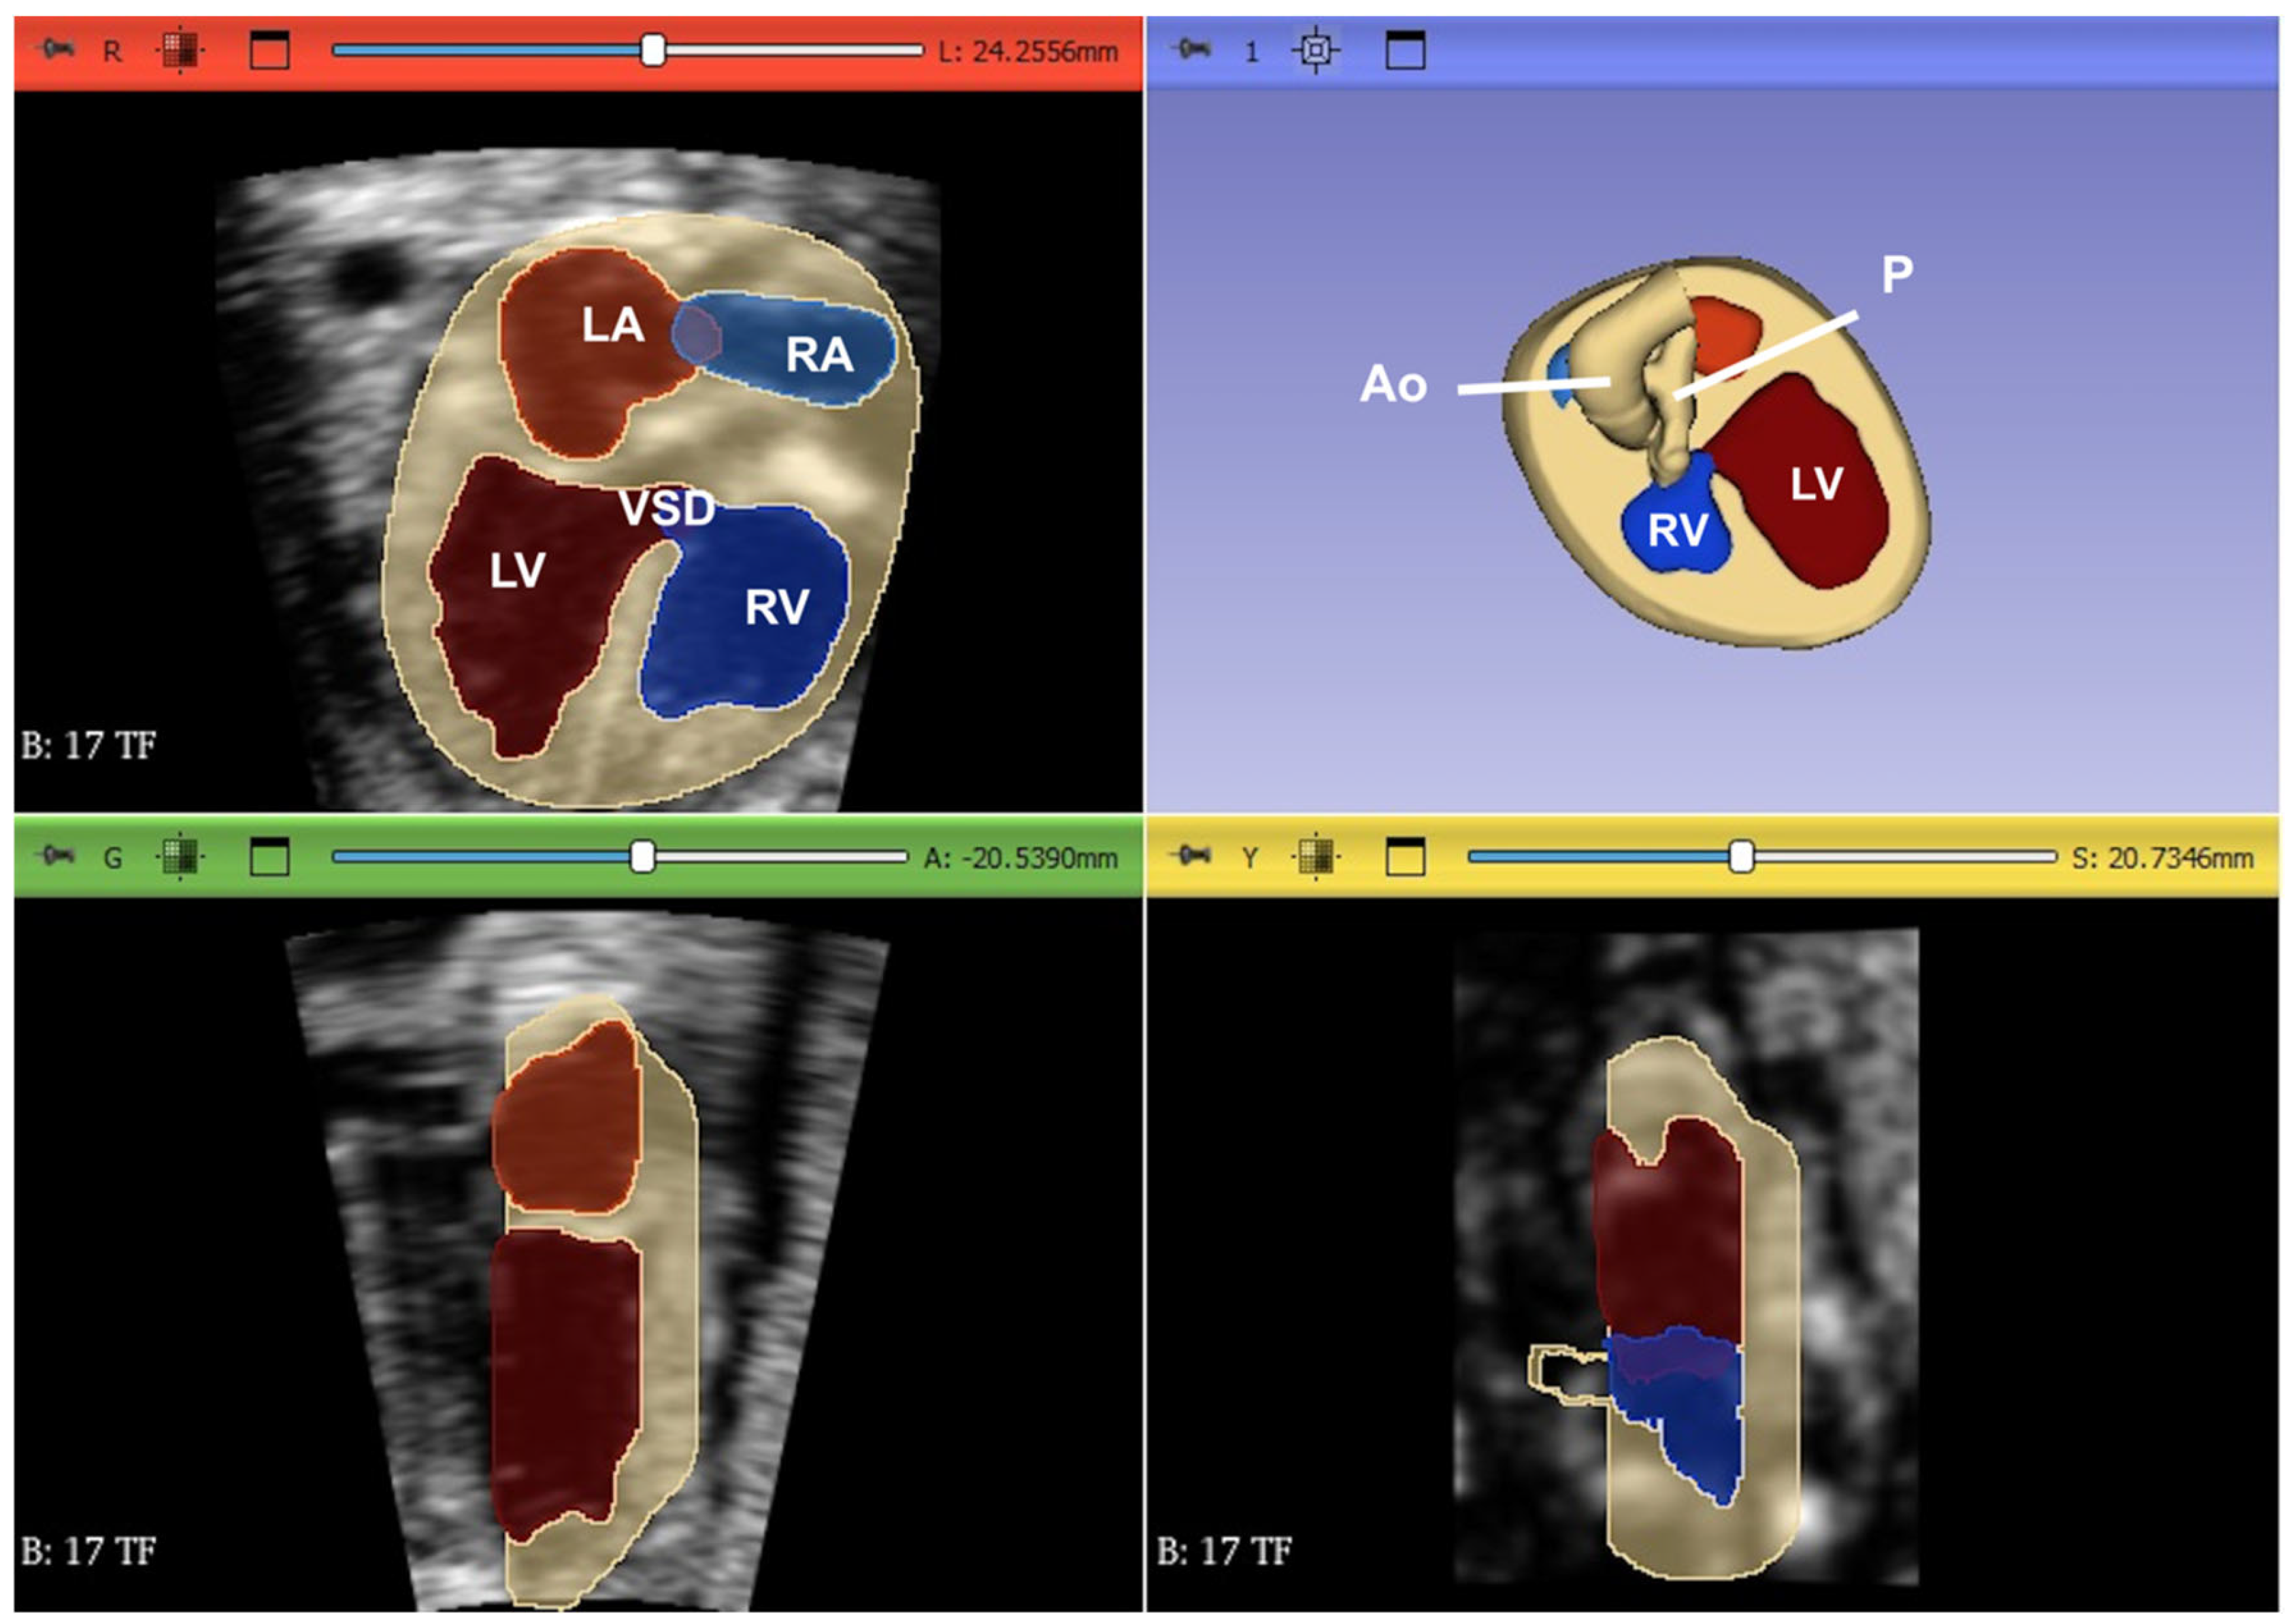

- Liu J, Wang Y, Zhao H, Liu W. Spatio-temporal image correlation rendering mode visualizes the specific location and surrounding structure of ventricular septal defect. Clin Anat. 2019, 32, 408–420.

- Malho A, Ximenes RS, Bravo-Valenzuela NJ, Araujo Júnior E. Spatio-Temporal Image Correlation: Three-Dimensional Imaging for Fetal Cardiac Screening and Congenital Heart Disease Assessment. Arq Bras Cardiol. 2024;121(4):e20230580.